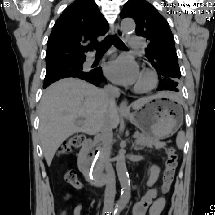

▲支架深嵌在胆管里

因此,老张只能通过外科手术开刀取出支架,但因其胆管直径较细,手术难度较大,强行拔除支架可能出现肠瘘、出血、胆管狭窄等危险。而且还要在两个不同的科室完成两次手术,不仅仅增加痛苦,更增加住院时间和医疗总费用。

经过详细的多学科讨论后,邱福南主任医师团队最终决定为老张实行胆道镜、胃镜、腹腔镜(三镜)直视下胆总管切开术取出结石及支架,术中探查见支架近端包埋于胆管、远端嵌顿于肠管,难度重重。